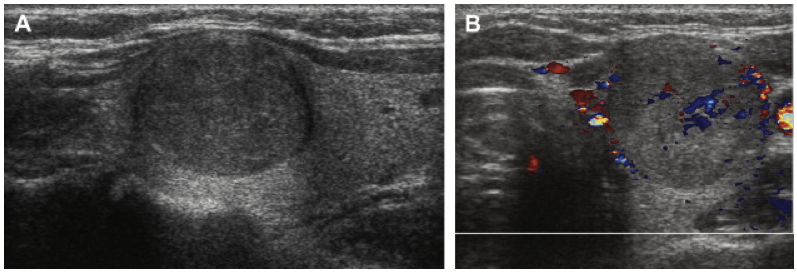

Des nodules peuvent apparaitre sur cette glande. Il s’agit de formations arrondies constituées de tissu thyroïdien ou de liquide. Ces nodules sont extrêmement fréquents et touchent plus de 1 personne sur 3 après l’âge de 50 ans.

Ils sont généralement indolores et ne provoquent aucun symptôme. Leur découverte se fait souvent par hasard, au cours d’une échographie du cou ou d’un scanner réalisées pour un tout autre motif.

Le cancer de la thyroïde ne provoque le plus souvent aucun symptôme. Ils sont découverts de façon fortuite lors d’un examen d’imagerie comme une échographie, un scanner ou une IRM réalisée pour une toute autre raison.

Le cancer peut être révélé par la présence d’un nodule de la thyroïde palpable ou visible. Plus rarement, il peut être révélé par un ganglion situé au niveau du cou ou par un trouble de la voix de la déglutition ou de la respiration qui sont liés à un envahissement du larynx ou de ses nerfs, de la trachée ou de l’œsophage. Des métastases situées dans les poumons ou les os peuvent aussi révéler la maladie.